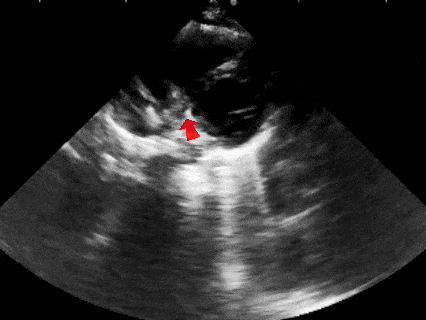

锁定后,超声下观察封堵器盘面平整贴壁,成型良好

锁定后牵拉

牵拉试验时,超声下观察封堵器,封堵器结构稳定无散开,锁定成功